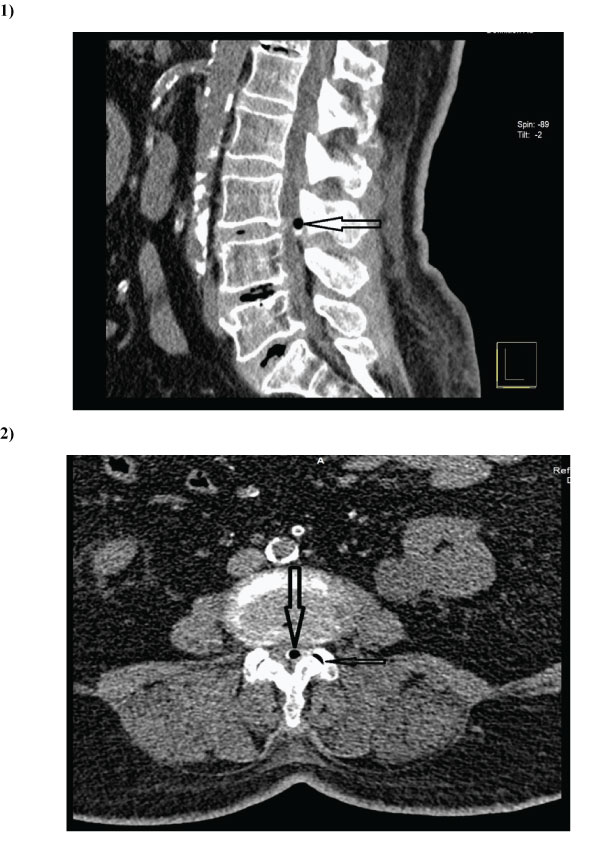

68-year-old women was admitted to the hospital with a low back pain radiating to her left leg for a week. She also complained of difficulties on walking for two years. On neurological examination, straight leg raising was positive at 45o on left. There was also a weakness of left knee extension with L4 hypoesthesia. Lumbar MRI showed a round hypointense lesion on both T1 and T2 weighted image adjacent to the left facet joint. There was no contrast enhancement following intravenous administration of contrast material. MRI appearance of the lesion suggested a calcified mass. On CT, a gas filled round synovial cyst with partially calcified wall was seen (Fig.1,2). Adjacent facet joint has also a vacuum sign. The patient underwent microsurgical removal of synovial cyst via L3 hemilaminotomy. A round mass with calcified wall compressing left L3 root removed. The wall of mass was not compressible due to calcification. All peripheral ligamentum flavum was also removed. Postoperative period was uneventful and symptoms were fully resolved in two months. Histopathological examination resulted in the diagnosis of synovial cyst.

Figure 1 and 2: Sagittal (1) and axial (2) CT scan slices show an air filled intraspinal mass with partially calcified wall at L3-4 level (big arrows). On axial slice, vacuum sign in the adjacent facet joint is seen (small arrow).